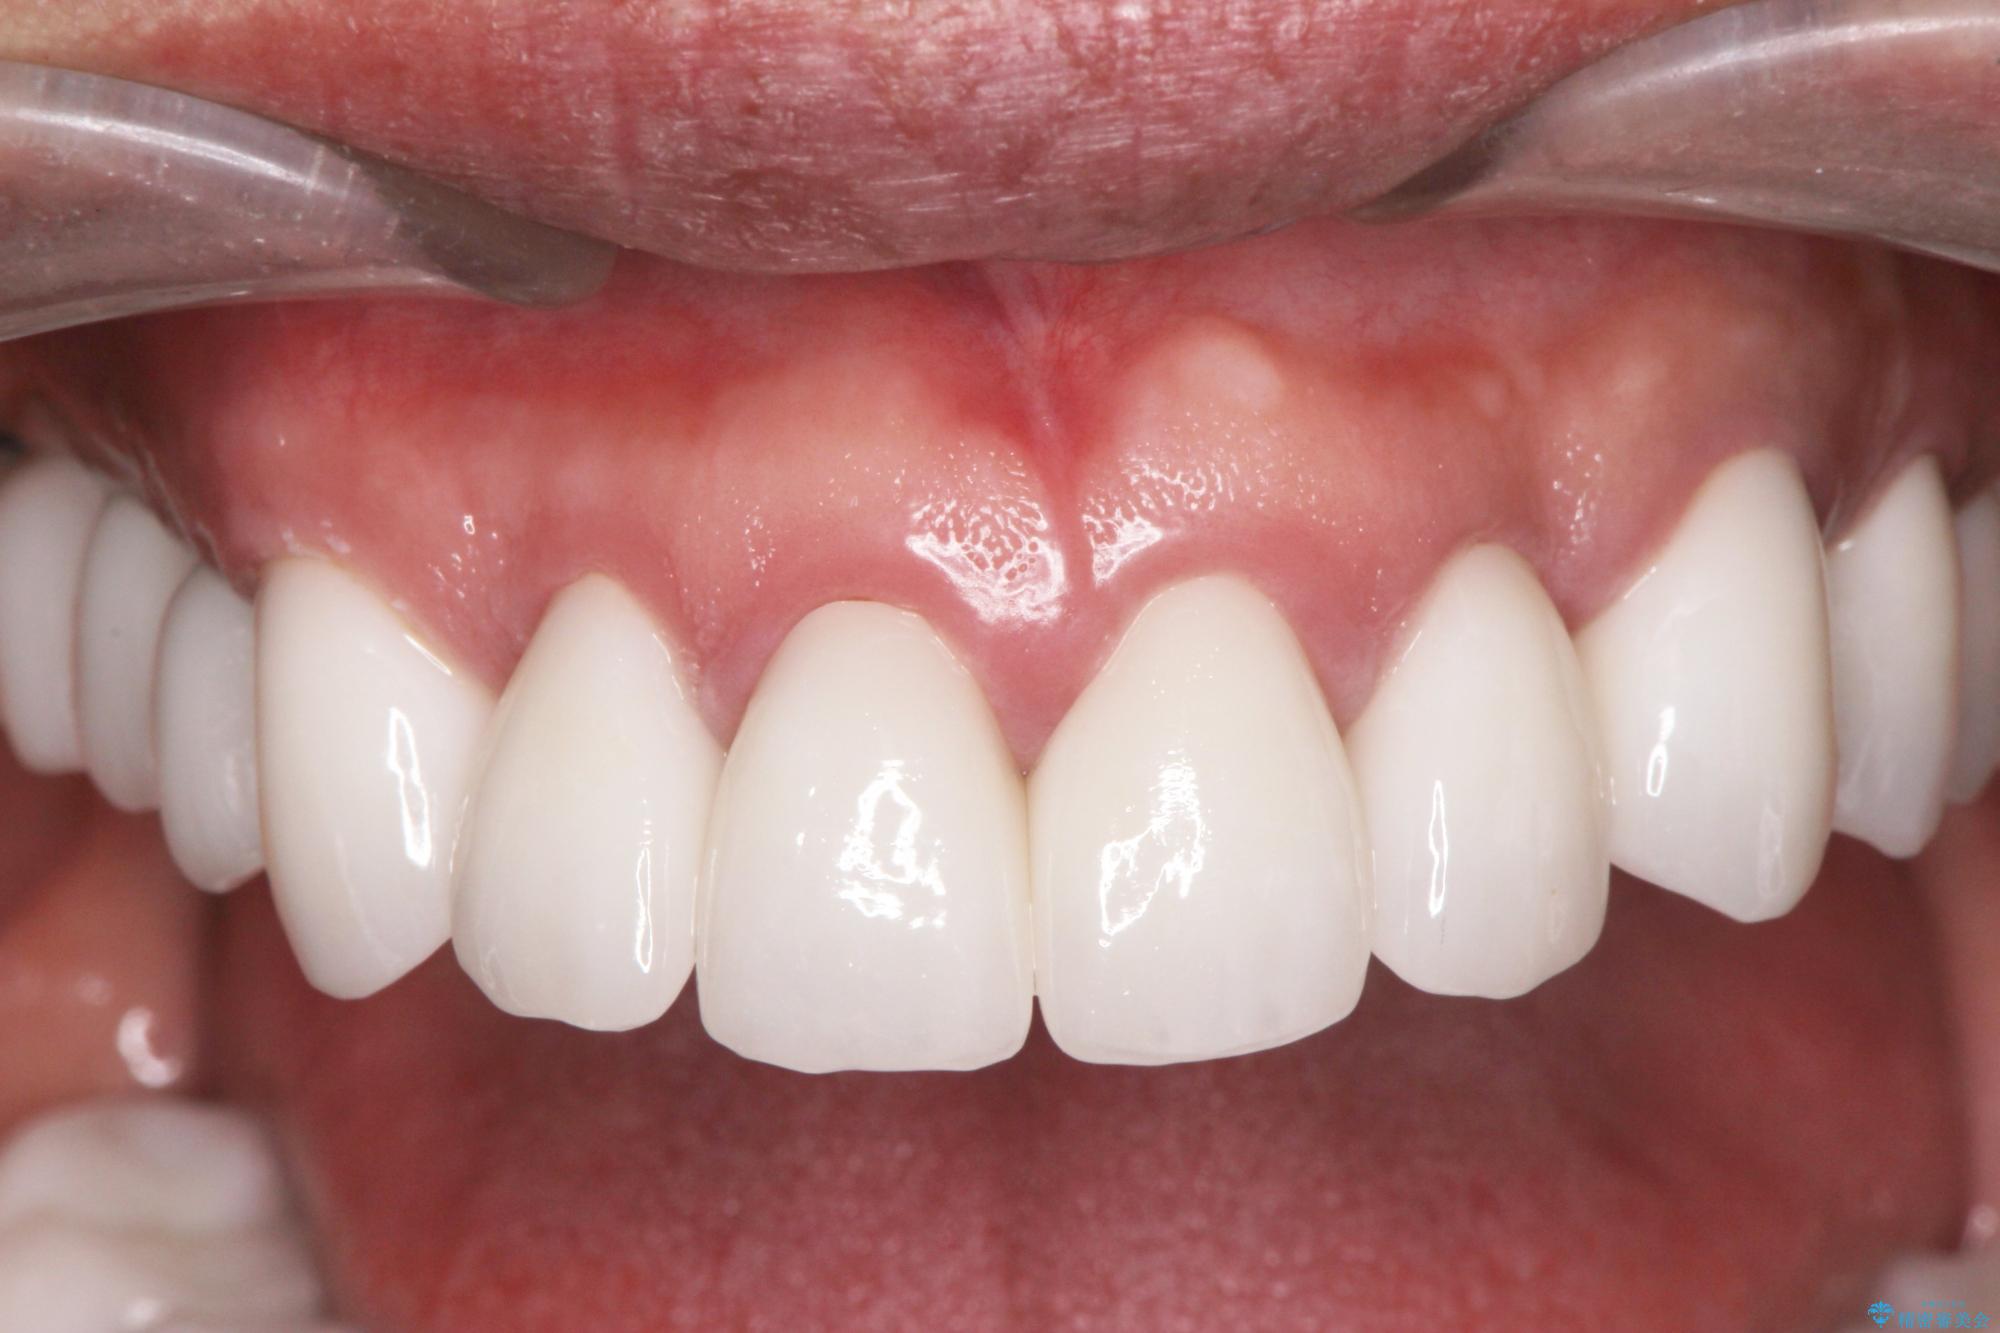

セラミッククラウンを除去し仮歯を装着し、歯周外科手術を行い歯ぐきの状態を改善したのち、適合の良いセラミッククラウンを再作製をする治療計画としました。

- 90.2万円(ジルコニアクラウン×6・仮歯×6 ・歯周外科手術)費用は治療当時の料金となります